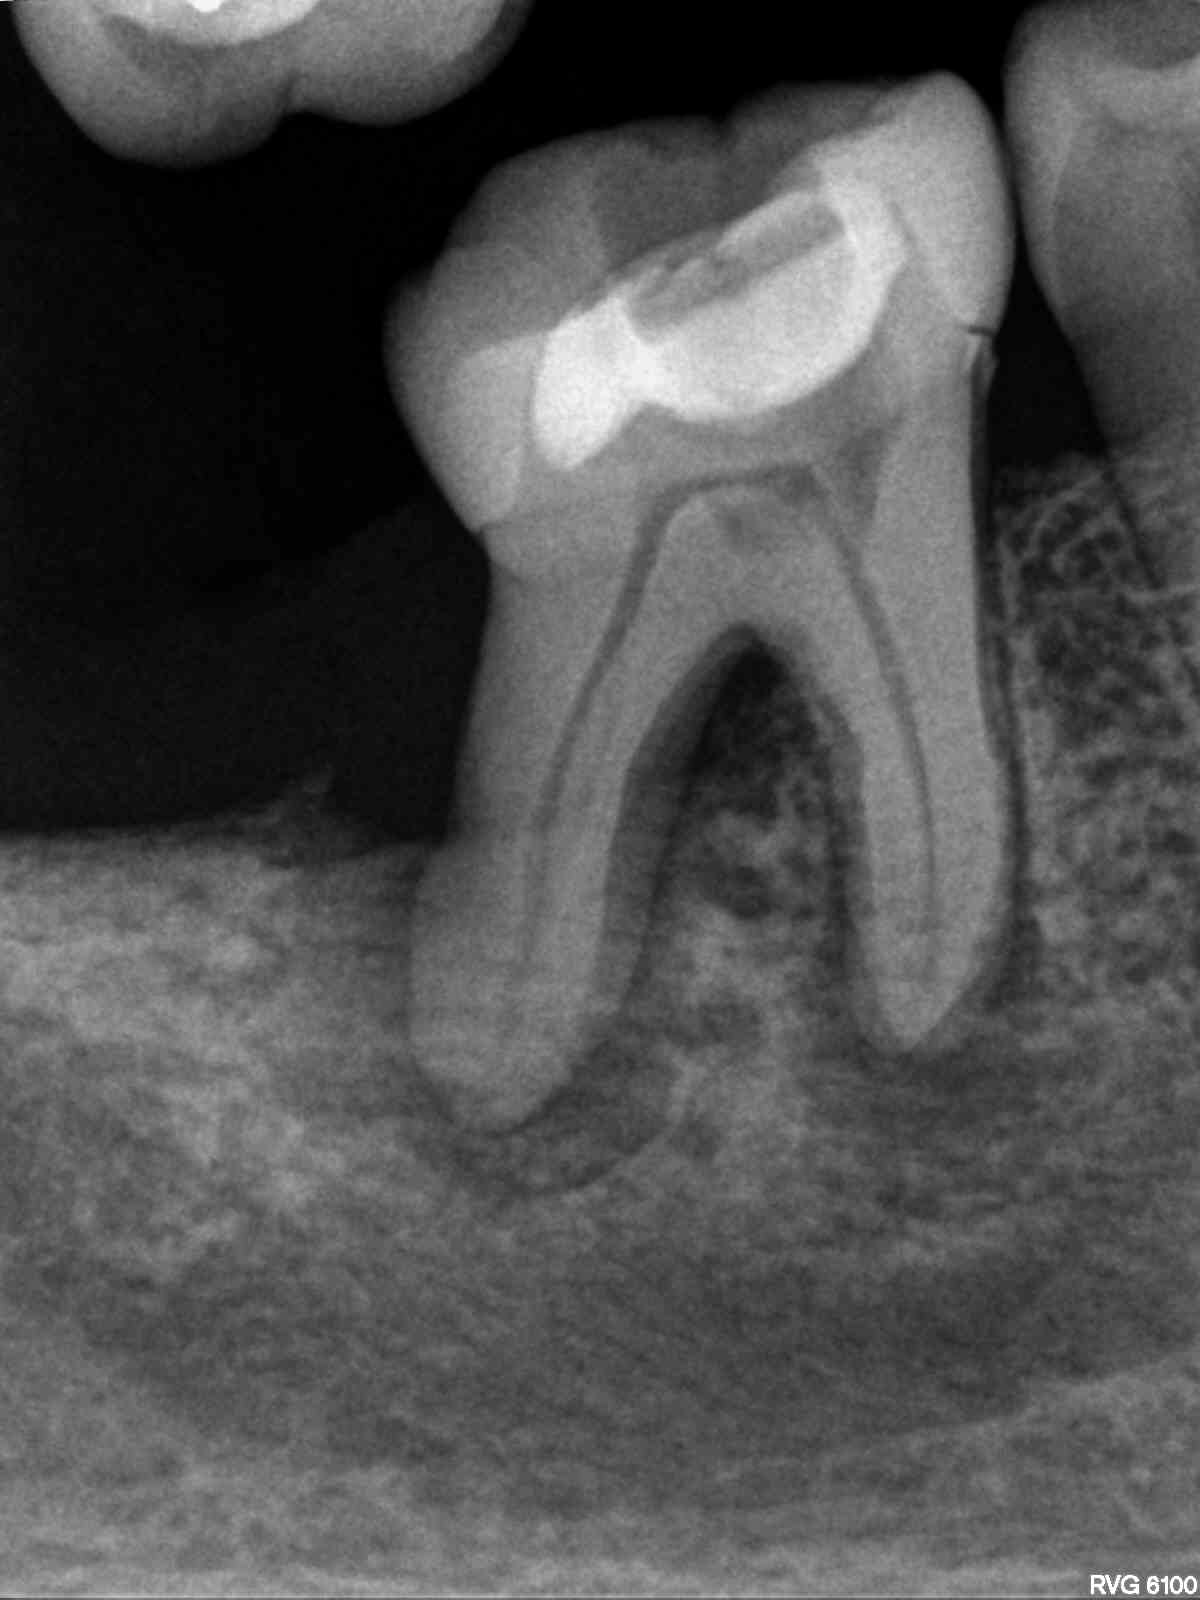

R2

1200 × 1600

Für oder Wider?